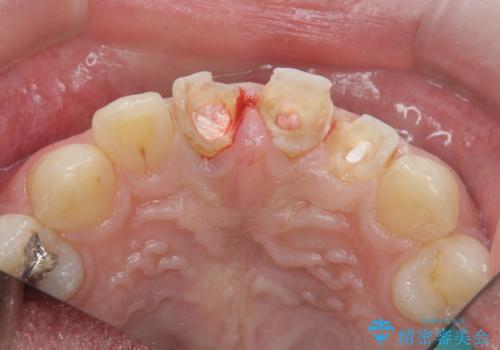

歯の挺出を行ったことで歯ぐきの腫れも改善され、安定した歯周環境下でのセラミッククラウン治療を行うことができました。